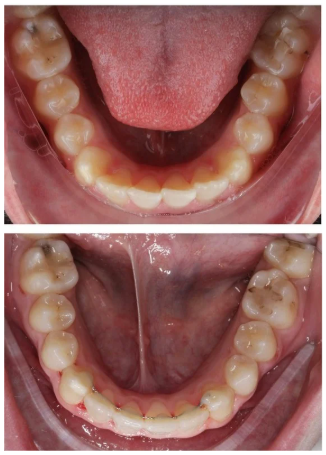

- Escaneado Digital Intraoral: Hemos sustituido las incómodas pastas de impresión por un escáner 3D. Obtenemos una réplica exacta de la boca del adolescente en segundos.